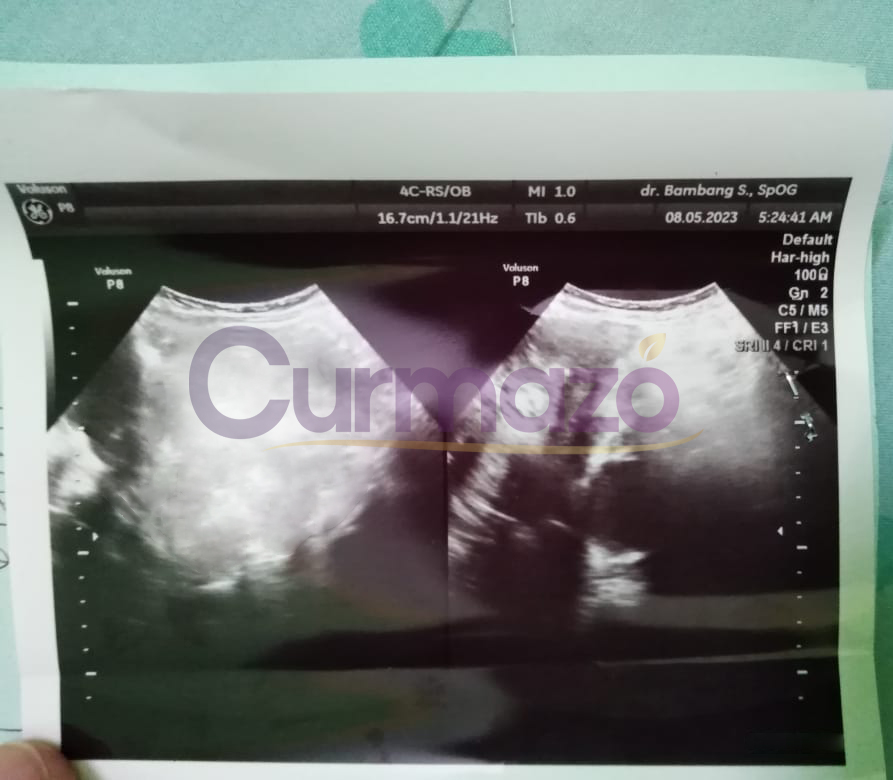

Hampir 4 bulan pengobatan saya sudah tidak merasakan gejala seperti sebelumnya, haid sudah lancar dan teratur. 8 Mei 2023 Saya coba menjalani pemeriksaan, hasilnya sangat luar biasa kista berukuran 7,76 x 9,56 cm tersebut hilang total.

28 April 2023, hampir 2 bulan pengobatan saya melakukan usg kembali. Hasilnya sangat mengejutkan, miom berukuran 10 cm yang selama ini menyiksa, hilang total!